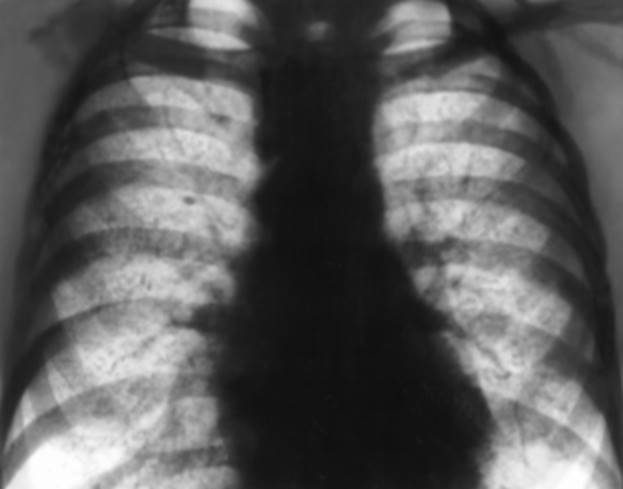

Рис. 12. Обзорная рентгенограмма грудной клетки больного идиопатическим гемосидерозом легких: мелкосетчатая диффузная деформация легочного рисунка, обусловленная уплотнением интерстициальной ткани легких, множественные рассеянные мелкие мономорфные очаговые тени.